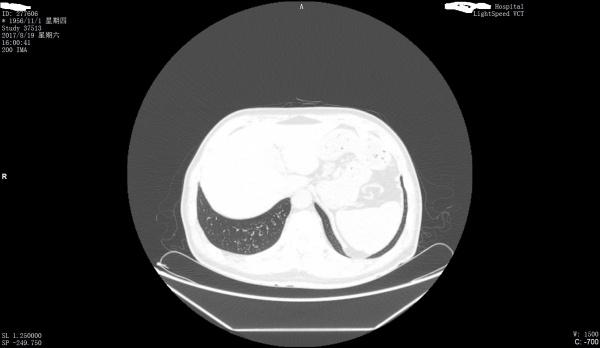

看看是否左膈肌出现胸腹膜裂孔疝